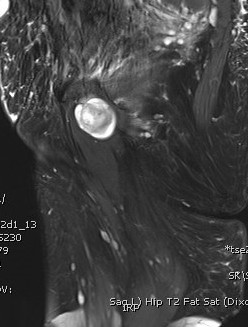

MRI

Target sign

- hypointense centrally

- hyperintense peripherally

Neurofibroma femoral nerve